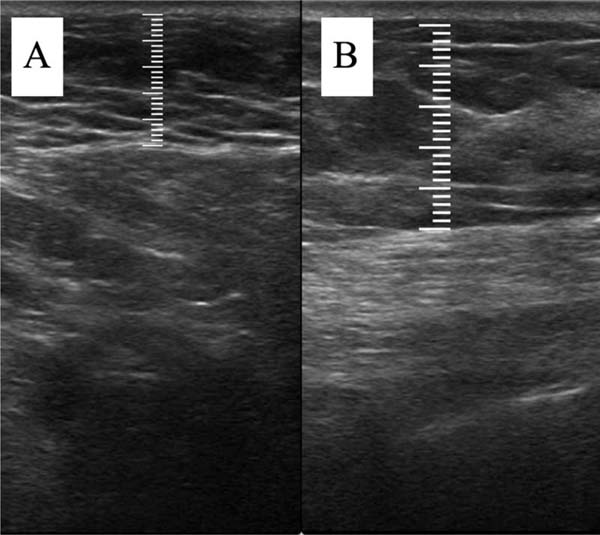

The measurement of subcutaneous tissue thickness is performed vertically, from the highest (right at the transition from the epidermis) to the lowest point (at the transition with the muscle tissue) of subcutaneous tissue thickness. This measurement is easily reproducible for those with basic ultrasound skills (►Fig. 2). In lipofilled breasts, the thickness of subcutaneous tissue was measured preoperatively and immediately after lipofilling, as well as at 15, 30, 90, and 180 days postoperatively. Measurements in millimeters were taken using ultrasound, including the vertical distance from the highest (closest to the epidermis) to the lowest point (closest to the adjacent musculature) of the subcutaneous tissue at the previously defined point. A GE LOGIQ P6 (GE HealthCare) ultrasound device with an 11L linear probe and a frequency range of 12 to 6 MHz was used, operated by a surgeon with postgraduate training in general ultrasonography (►Fig. 3).